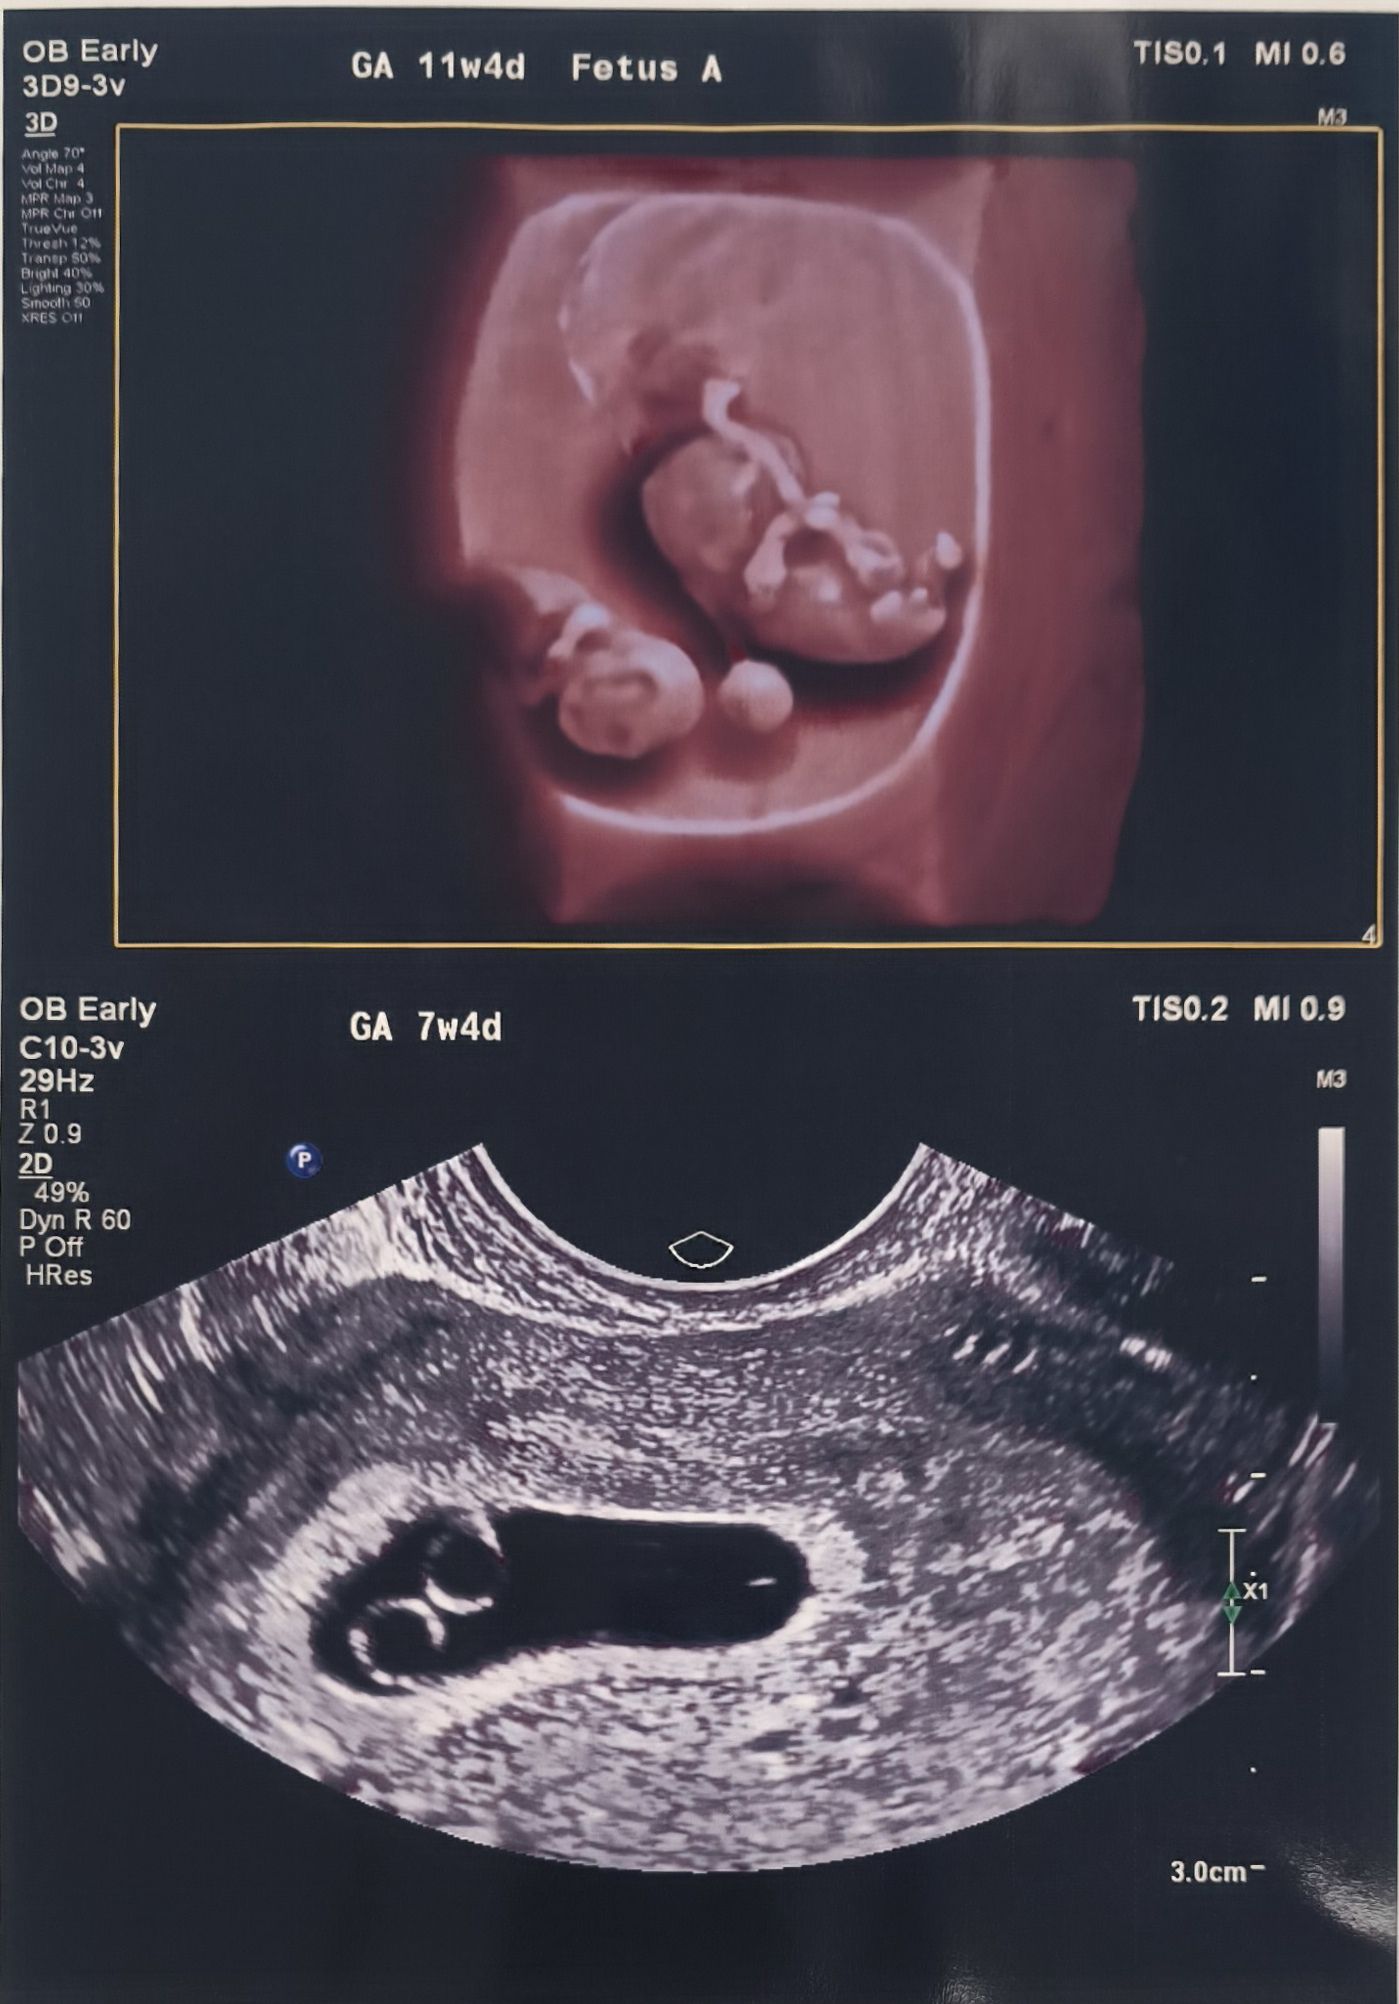

ΕΞΕΙΔΙΚΕΥΜΕΝΗ ΠΑΡΑΚΟΛΟΥΘΗΣΗ ΑΡΧΙΚΗΣ ΚΥΗΣΗΣ

Η αρχική κύηση αποτελεί την πιο κρίσιμη και ευαίσθητη περίοδο της εγκυμοσύνης, κατά την οποία τίθενται οι βάσεις για την ομαλή εξέλιξή της. Η εξειδικευμένη παρακολούθηση πρώτου τριμήνου απευθύνεται σε φυσιολογικές, αλλά και υψηλού κινδύνου ή παθολογικές κυήσεις, με στόχο την έγκαιρη διάγνωση, την πρόληψη επιπλοκών και τη μείωση της αγωνίας των γονέων.

Με πολυετή εμπειρία στην καθοδήγηση μονάδων γονιμότητας και πρώιμης κύησης σε διεθνές επίπεδο, η υπηρεσία παρέχει ολοκληρωμένη αξιολόγηση από την προ-σύλληψη έως τις πρώτες κρίσιμες εβδομάδες της εγκυμοσύνης, περιλαμβάνοντας τη διαχείριση:

Η προηγμένη υπερηχογραφική απεικόνιση επιτρέπει:

— Πολύ πρώιμη και ασφαλή επιβεβαίωση της ενδομήτριας κύησης

— Απεικόνιση του εμβρυϊκού σάκου και του πρώιμου εμβρύου με χαμηλή ενεργειακή επιβάρυνση

— Έγκαιρη διάγνωση πολύδυμης κύησης και καθορισμό τύπου

— Δυναμική αξιολόγηση σε γυναίκες με συνυπάρχουσες παθολογίες (κύστεις ωοθηκών, τραχηλική ανεπάρκεια, ανατομικές ιδιαιτερότητες μήτρας)

Η παρακολούθηση μπορεί να ξεκινήσει εξαιρετικά νωρίς, ήδη από τις πρώτες εβδομάδες μετά τη θετική δοκιμασία κύησης, παρέχοντας σαφείς απαντήσεις σε μια περίοδο που συχνά χαρακτηρίζεται από αβεβαιότητα.